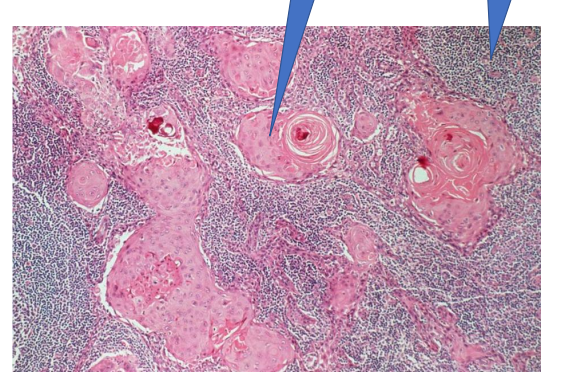

Squamous cell carcinoma

1- Squamous epithelium

2- Ivasion of Tumor to CT

3- Tumor island with keratin pearl

normal lymph node

Lymph node w metastases

1- squmous cell carcinoma island

2- normal myphoid tissue